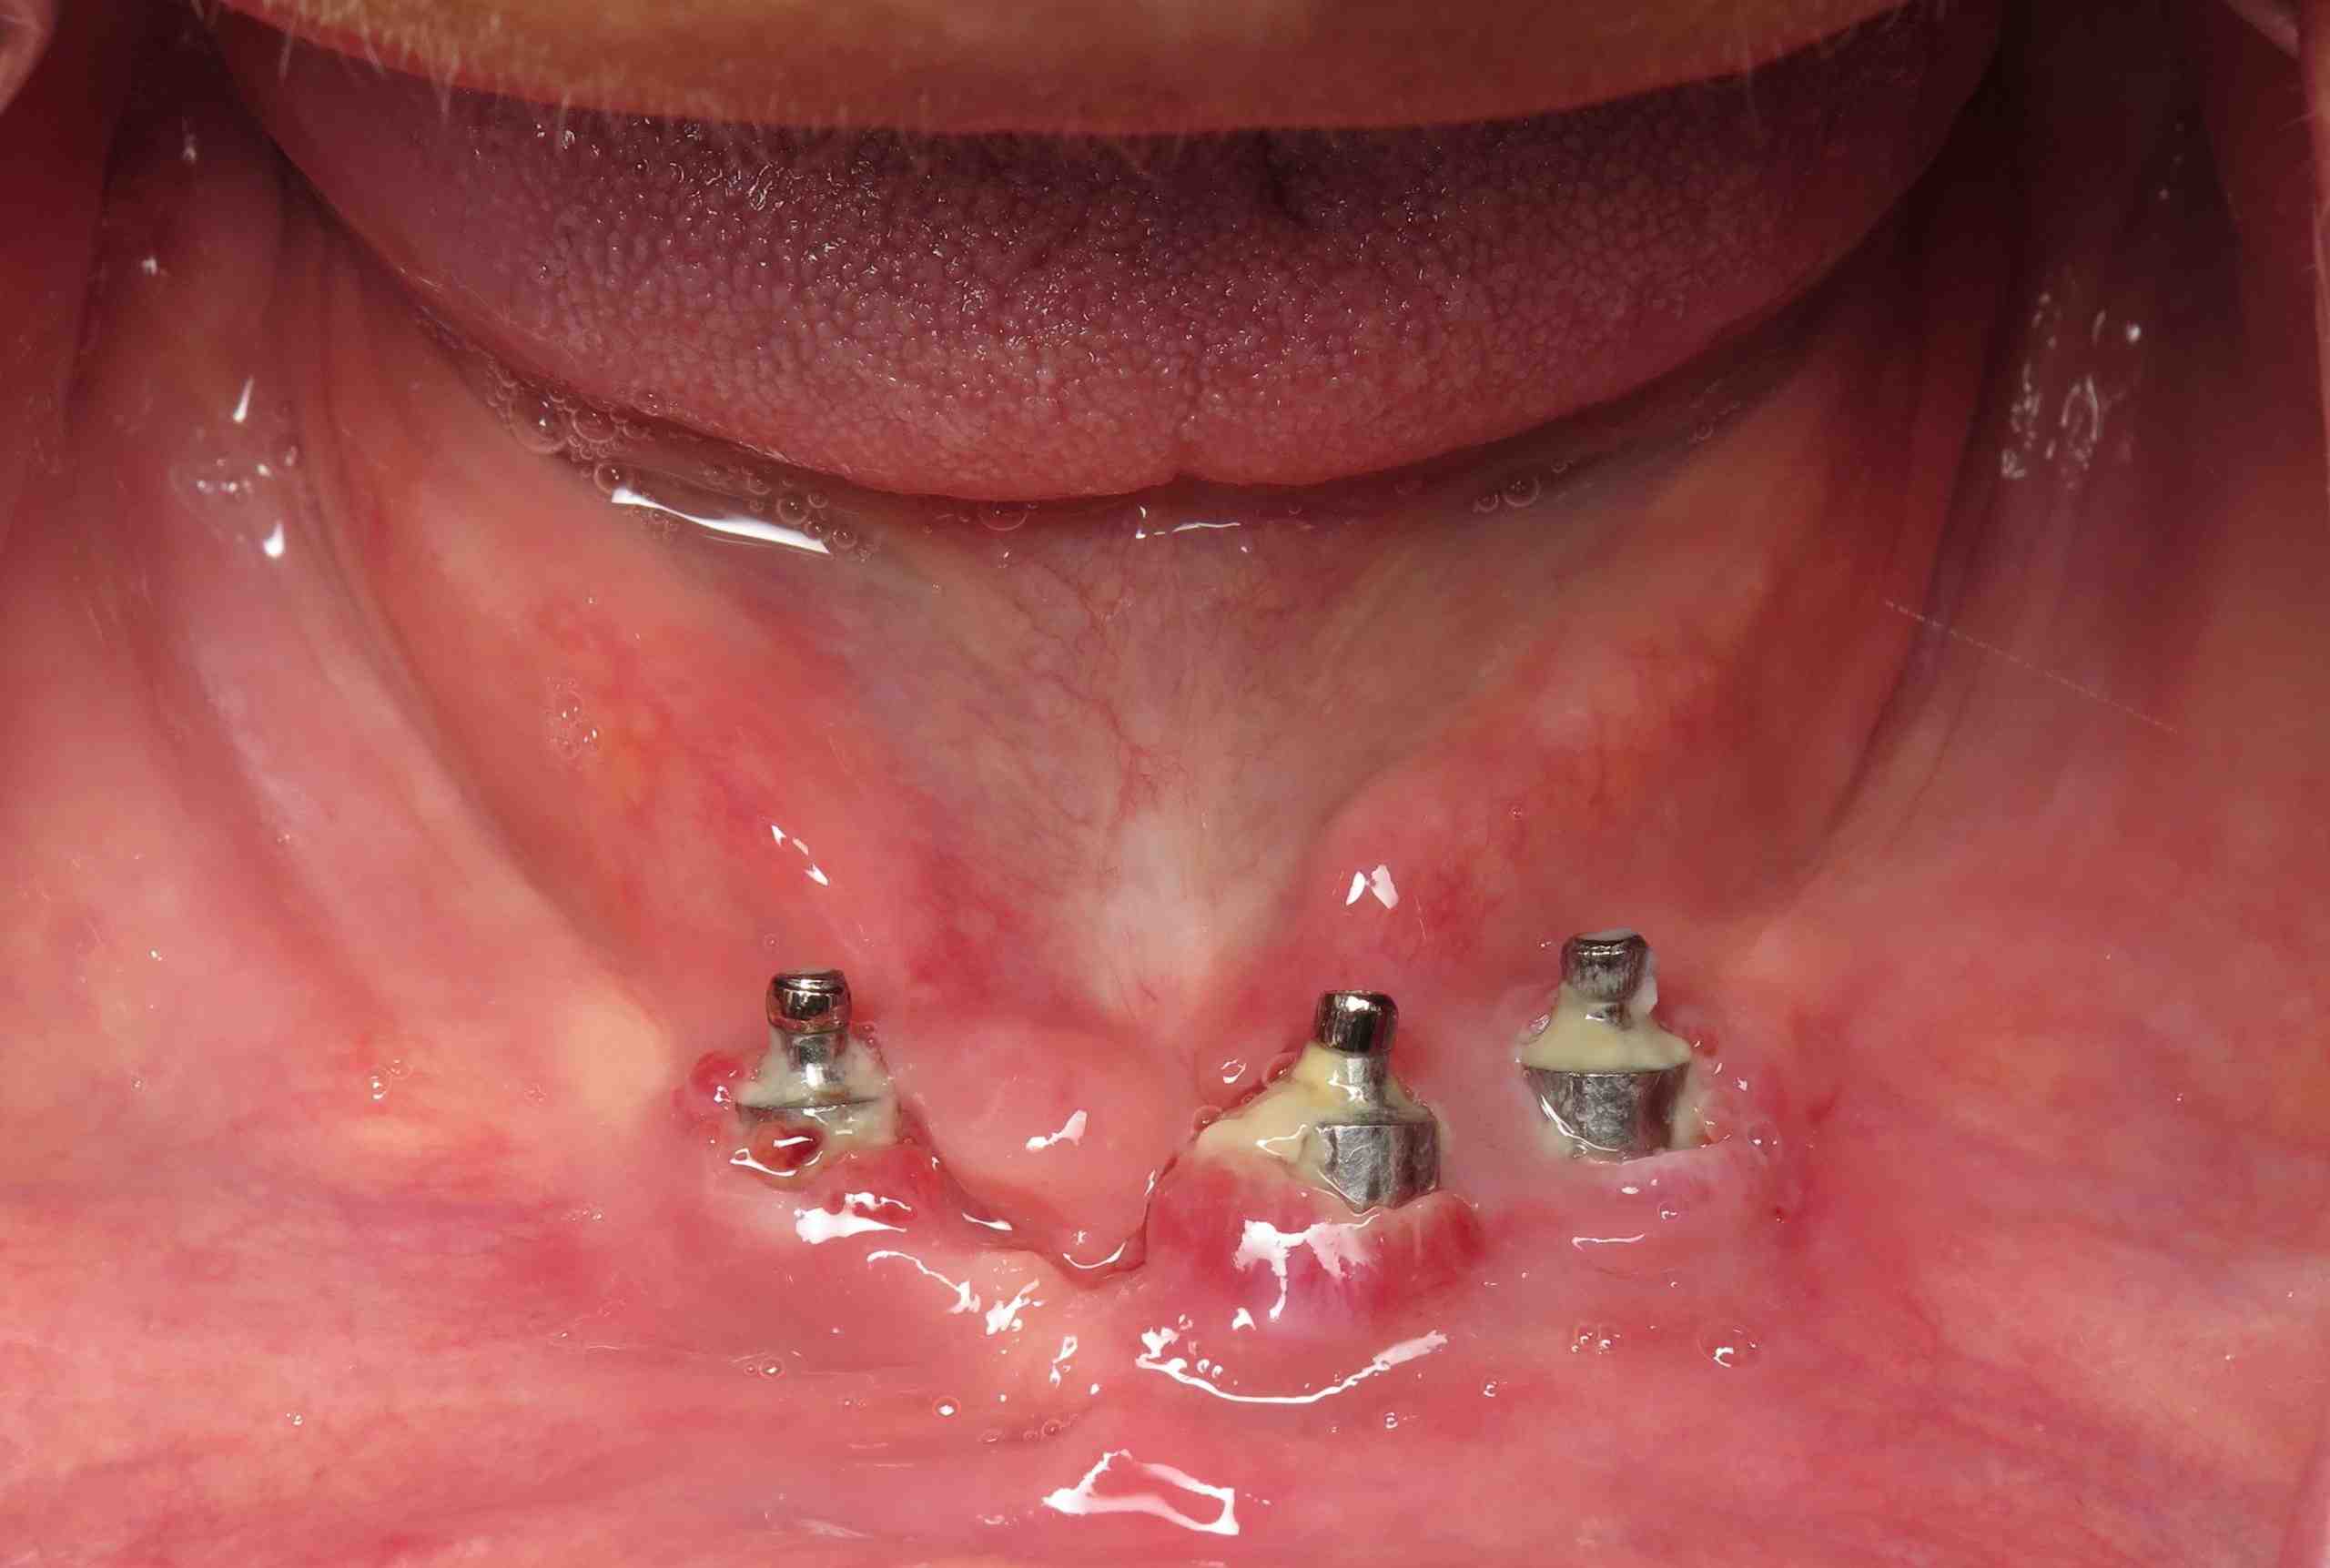

What causes bone loss around an implant?

How much bone loss around implant is normal?

Bone loss around dental implants is usually measured by changes in the marginal bone level with X-rays. After the first year of implantation, an implant & lt; 0.2 mm annual loss of marginal bone level have to meet the criteria of success.